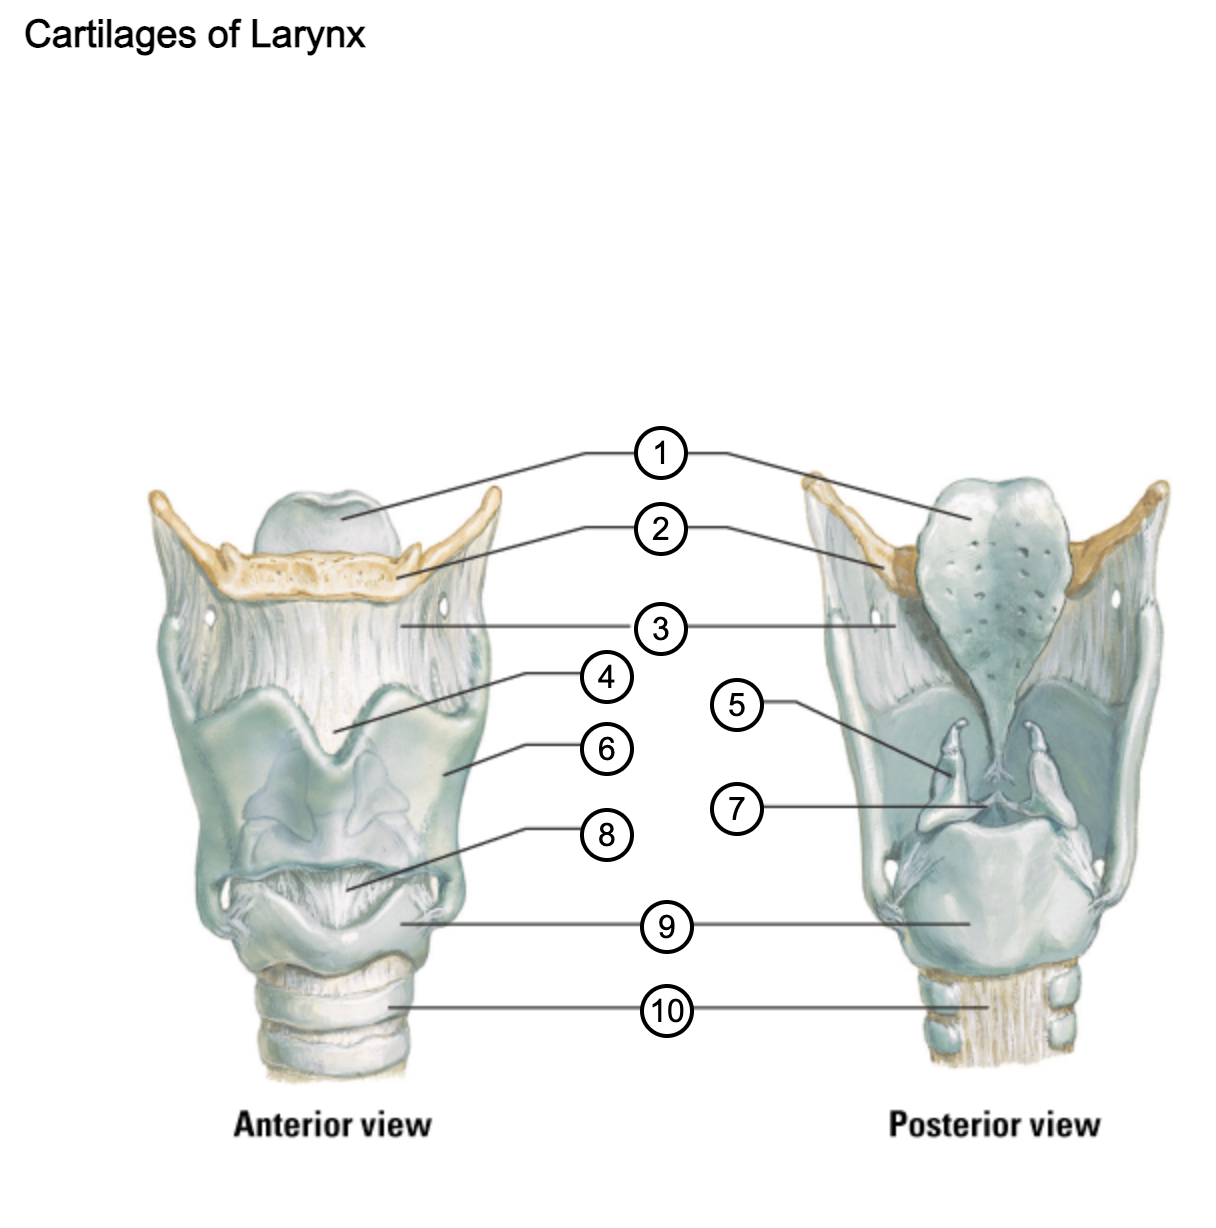

1

epiglottis

2

hyoid bone

3

thyrohyoid membrane

4

superior thyroid notch

5

arytenoid cartilage

6

lamina of thyroid cartilage

7

vocal ligament

8

median cricothyroid ligament

9

cricoid cartilage

10

trachea